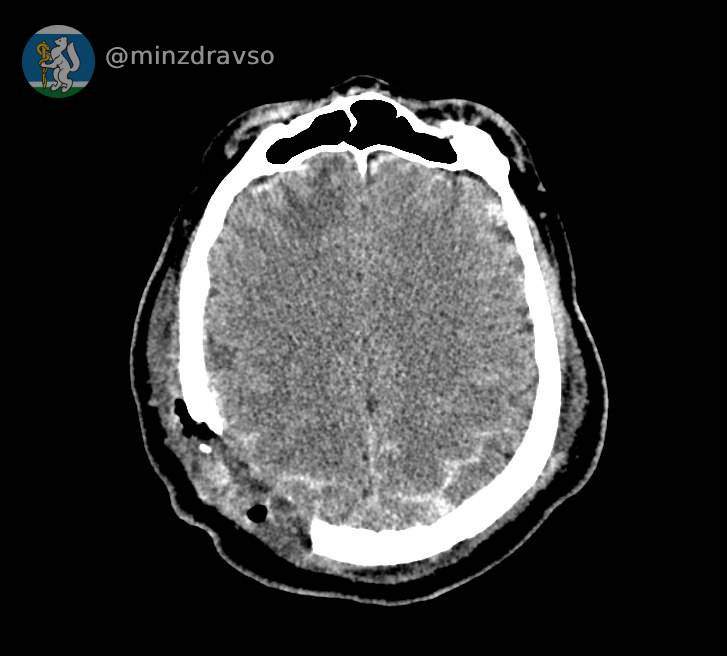

В Свердловской области благодаря усилиям врачей из Серова, Нижнего Тагила и Екатеринбурга удалось спасти 57-летнего мужчину, пострадавшего от удара по голове стрелой строительного крана.

Как рассказали на информационном портале регионального Минздрава «Здоровье уральцев», у мужчины была тяжелейшая черепно-мозговая травма. Любой из осколков черепа, повредивших мозг, мог стать причиной смерти.

Провести компьютерную томографию, чтобы понять, как именно раскололся череп, и стабилизировать состояние пациента оперативно смогли врачи Серова. Затем, после консультации с профильными специалистами из Екатеринбурга, мужчину экстренно перевезли в больницу Нижнего Тагила, где его уже ждала операционная бригада: врачи удалили осколки костей и восстановили целостность твёрдой мозговой оболочки.